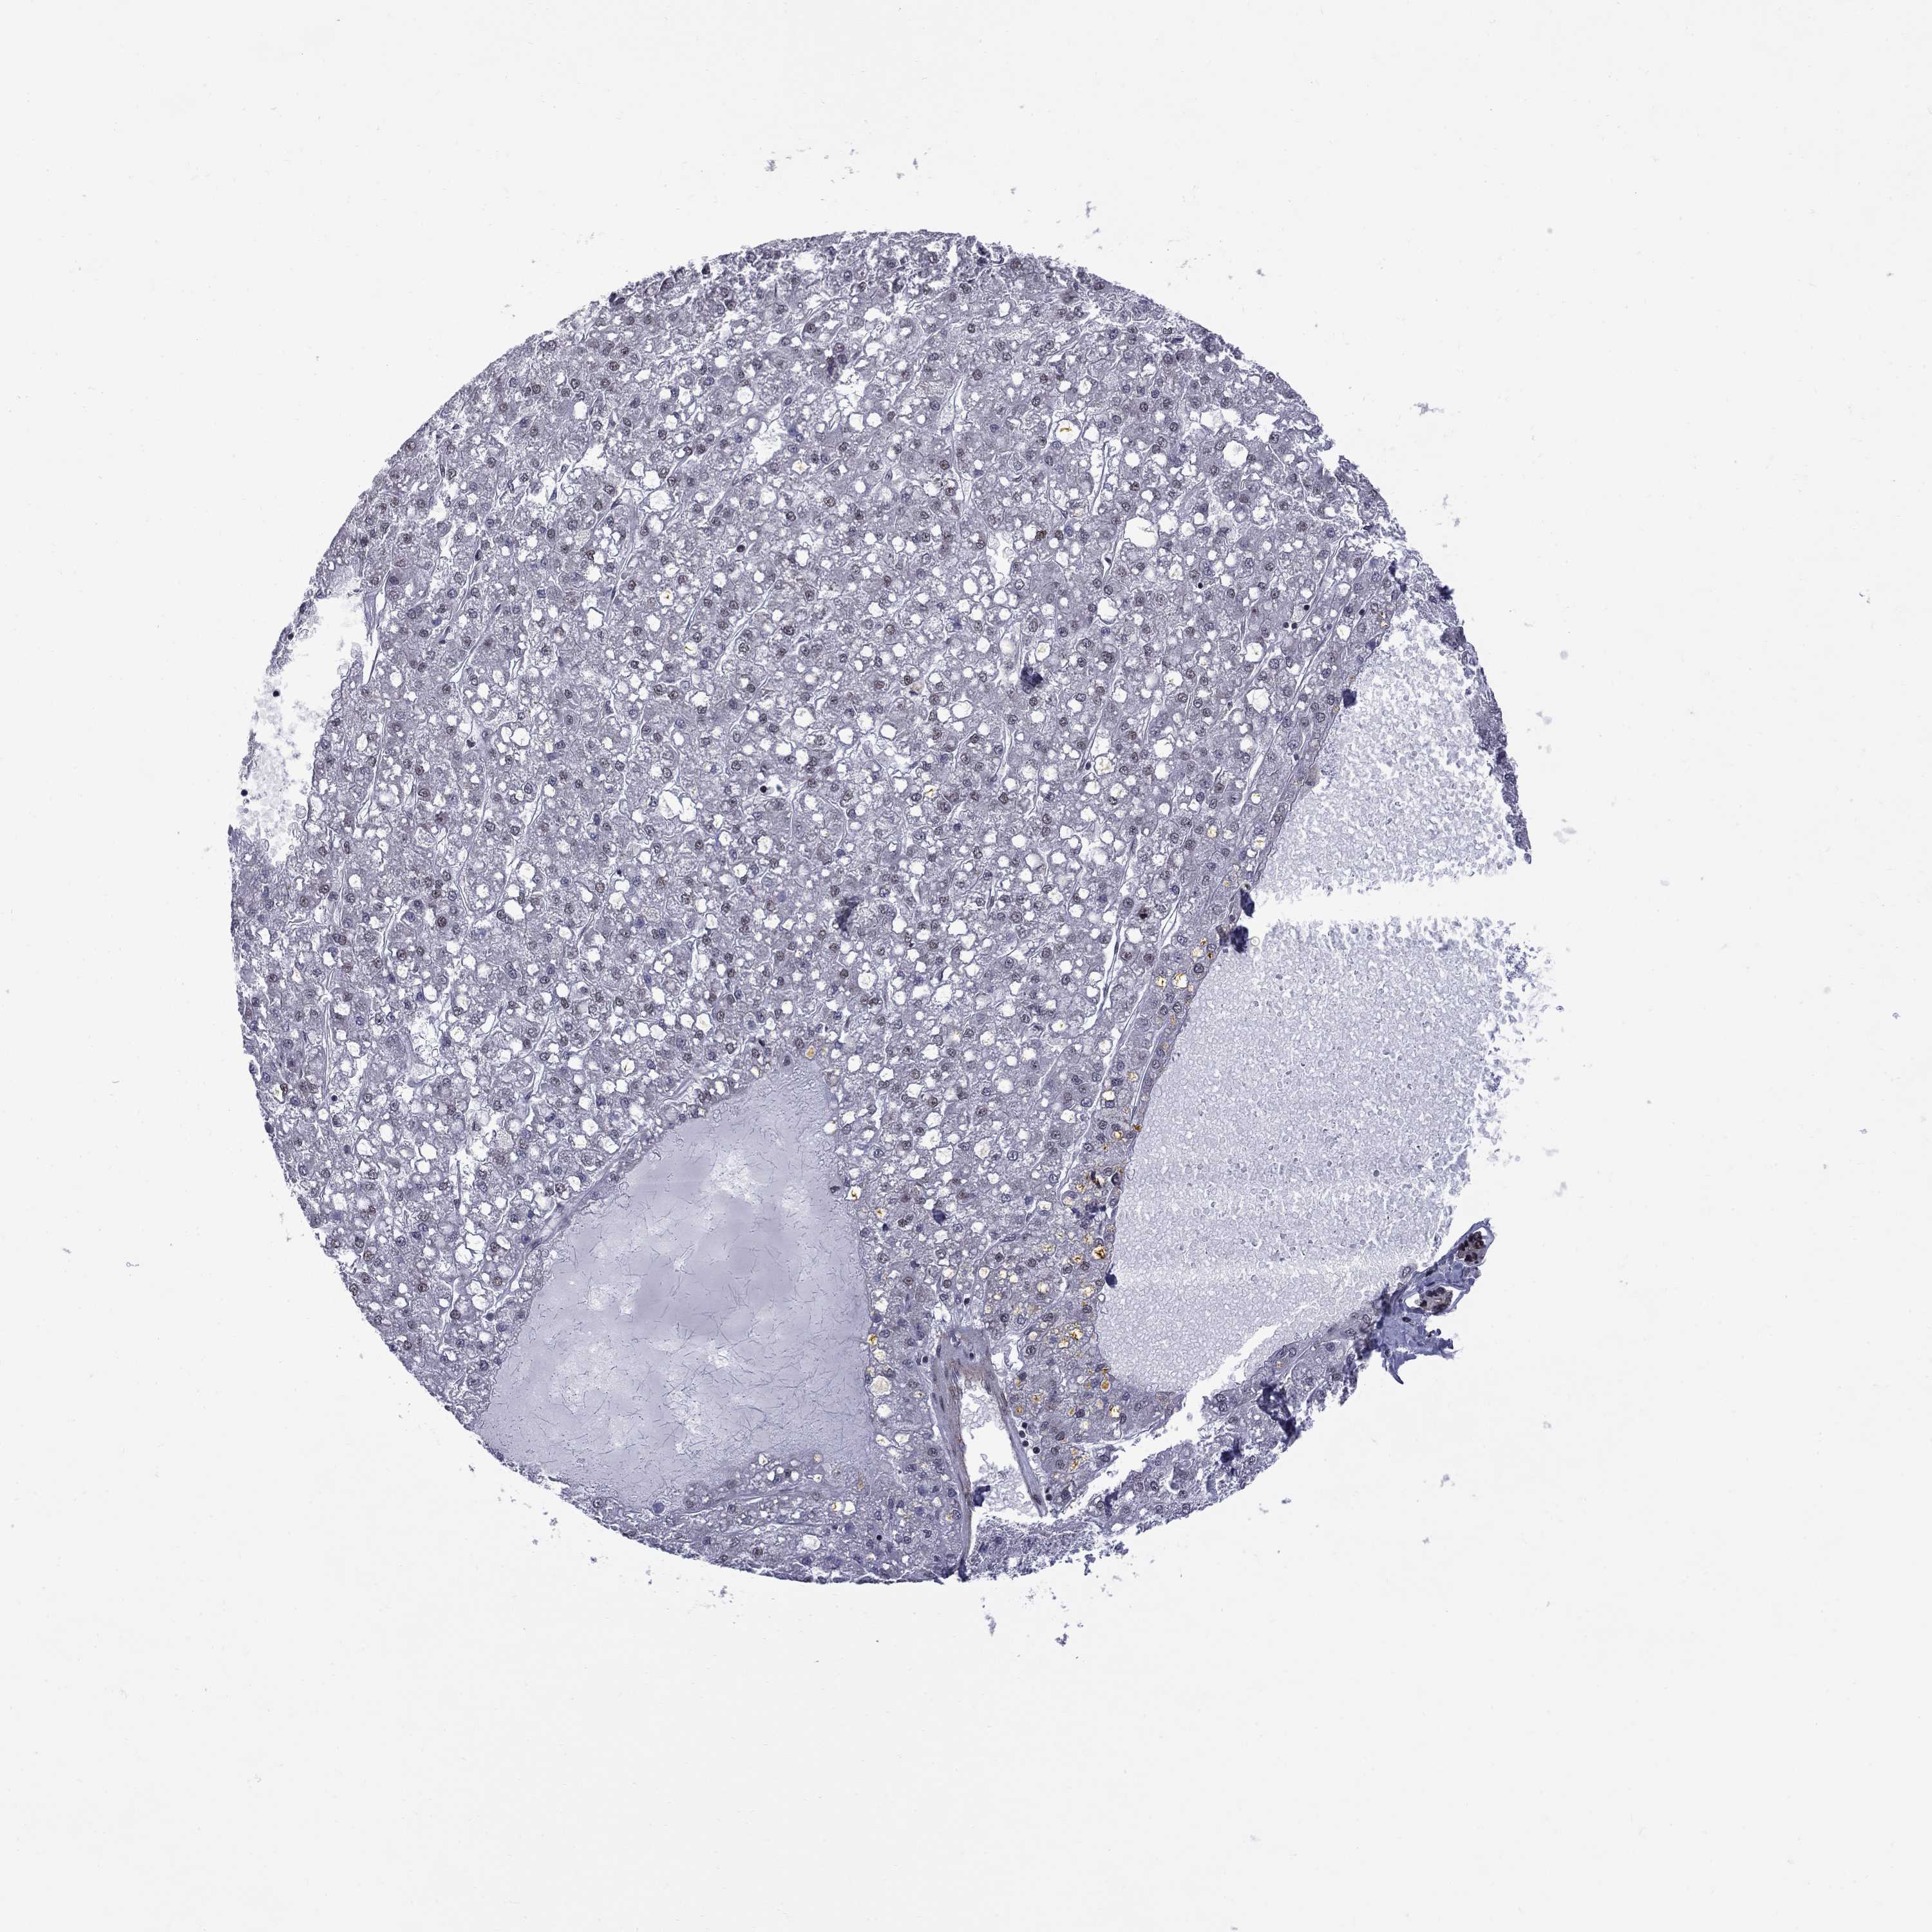

LIVER CANCER - Protein expressioni

A mouse-over function shows sample information and annotation data. Click on an image to view it in a full screen mode. Samples can be filtered based on level of antibody staining by selecting one or several of the following categories: high, medium, low and not detected. The assay and annotation is described here.

Note that samples used for immunohistochemistry by the Human Protein Atlas do not correspond to samples in the TCGA dataset.

Antibody stainingi

Antibody staining in the annotated cell types in the current human tissue is reported as not detected, low, medium, or high, based on conventional immunohistochemistry profiling in selected tissues. This score is based on the combination of the staining intensity and fraction of stained cells.

Each image is clickable and will lead to virtual microscopy that enables deeper exploration of all samples and also displays staining intensity scores, fraction scores and subcellular localization as well as patient and tissue information for each sample.

Antibody HPA074990

Staining

High

Medium

Low

Not detected

Intensity

Strong

Moderate

Weak

Negative

Quantity

>75%

75%-25%

<25%

None

Location

Nuclear

Cytoplasmic/membranous

Cytoplasmic/membranous,nuclear

Carcinoma, Hepatocellular, NOS